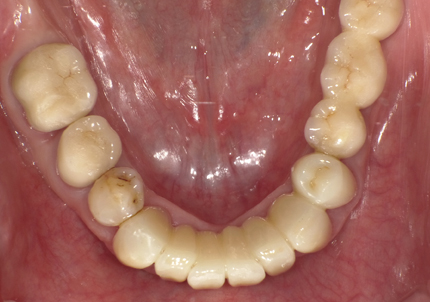

9.左下3本最終補綴装着(2021年11月)

10.口腔内写真(2022年2月)

特に問題無く経過はとても良いです。

患者様ご本人も「良く咬めてとても良い」と満足されています。

11.口腔内写真(2025年6月)

右下2本初診より9年経過、左下3本埋入後4年経過、ともに経過良好。